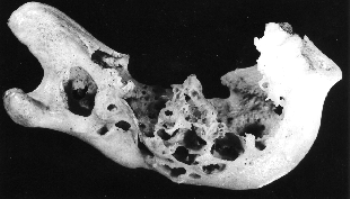

- Mandible with amelioblastoma

- GC.4823

- Mandible, macerated left half of an adult, shoving changes due to epithelial o don tome. The tumour has produced an irregular excavation of the ramus by decalcification and expansion anteriorly. The rest of the tumour wail has been reduced to fibrous tissue and the numerous cup-shaped depressions in the bone indicate the formation of fibro-osseous septa within the tumour.